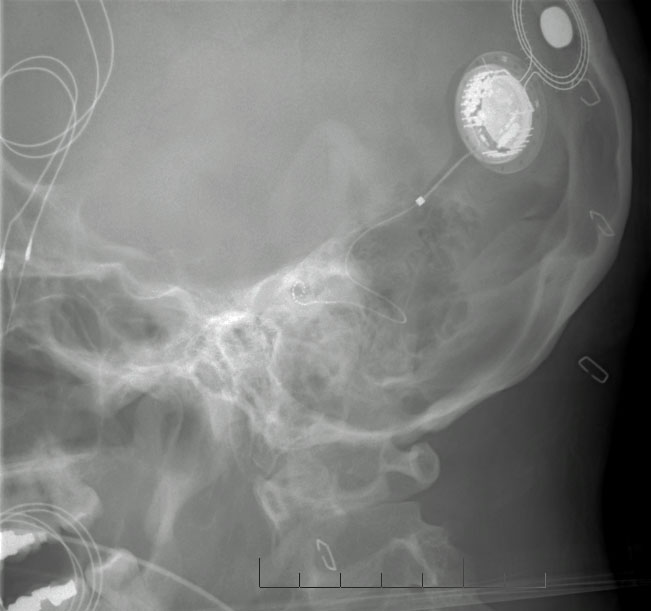

From lnh.edu.pk

Internal Part How Painful Is Cochlear Implant Surgery With general anesthesia you feel no pain. What can i do about it? Speech processors are often heavier than hearing aids, and ear soreness while using them — especially in the beginning — is common. At the start of cochlear implant surgery, patients are given general anesthesia, so they won’t be awake or feel pain during the procedure. Moleskin, often. How Painful Is Cochlear Implant Surgery.